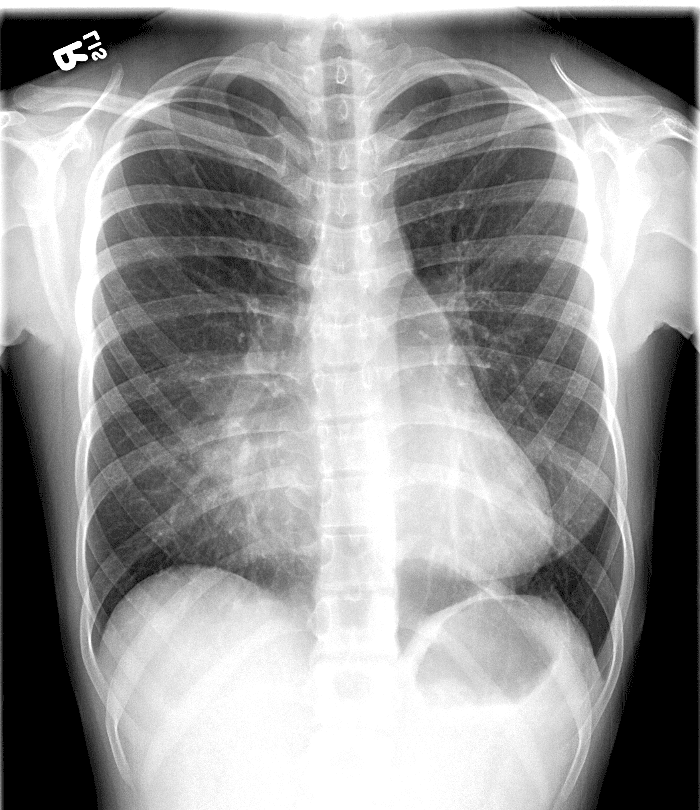

Practice Cases